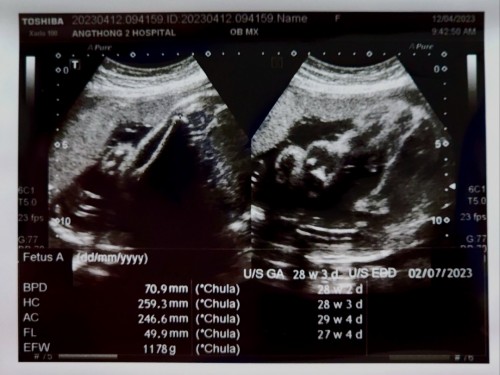

27w น้องนน.เท่าไหร่กันบ้างค่ะแม่

27w น้องนน.เท่าไหร่กันบ้างค่ะแม่ จะควบคุมนน.ตัวเองยังไง ไม่ให้ขึ้นเยอะ ลดของหวาน ทอด ลดข้าวแล้ว ตรวจน้ำตาลรอบแรกแล้วไม่ผ่าน

23w4d น้องหนัก 749g ค่ะแม่